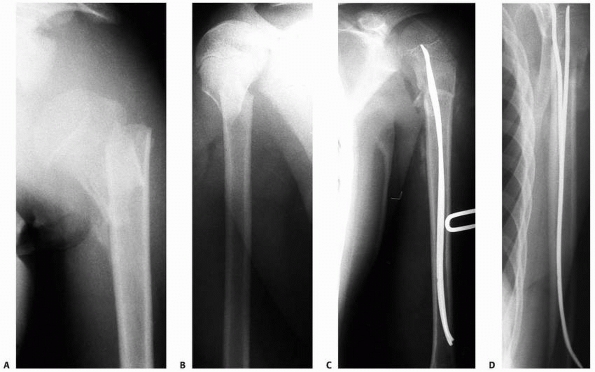

middle third clavicular fractures include severely displaced and

However, a prospective, randomized study reported that operatively

treated adult clavicle fractures had improved functional outcomes,

decreased time to union, and fewer symptomatic malunions and nonunions

than those treated nonoperatively with a sling.84

While the patients treated operatively also had more hardware-related

complications, the study supported primary plate fixation of midshaft

clavicle fractures in adults. Therefore, internal fixation can be

offered to active, skeletally mature adolescents and young adults with

displaced diaphyseal clavicle fractures (Fig. 17-8).